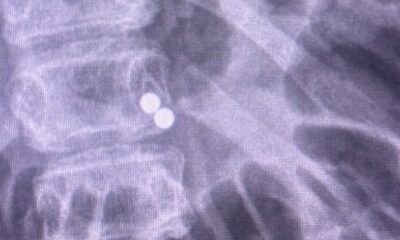

A 13-year-old boy required urgent surgery at Tauranga Hospital in New Zealand after swallowing nearly 100 magnets. The situation escalated quickly, necessitating a significant surgical intervention that involved the removal of part of his bowel.

The incident occurred when the boy ingested multiple small magnetic objects, which posed serious health risks. Medical experts warn that swallowing such items can lead to severe complications, including intestinal blockage and perforation. In this case, the magnets attracted each other within the boy’s digestive system, creating a chain reaction that caused significant damage.

Dr. Andrew Wills, a member of the medical team at Tauranga Hospital, described the procedure as a “major surgery.” He emphasized the urgency of the situation, stating that timely intervention was crucial to prevent further health complications. The surgical team worked meticulously to address the internal injuries caused by the magnets.